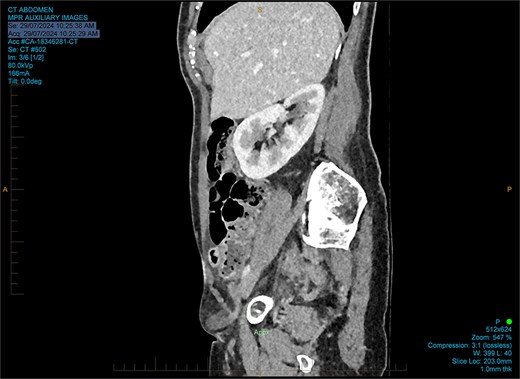

The working radiological diagnosis was an incarcerated Amyand’s hernia. However on examination, the lump appeared to be below the inguinal ligament more in keeping with a femoral hernia. Therefore under general anaesthesia, a high approach was taken. This revealed a femoral hernia under the inguinal ligament. Rectus sheath was opened transversely. A preperitoneal reduction was unsuccessful so peritoneum was opened in the right iliac fossa. This revealed an appendix incarcerated in the femoral hernia. The hernia was reduced revealing a grossly inflamed appendiceal tip (Fig. 3). An open appendicectomy was done, the hernia was closed with an intraperitoneal 1–0 Ethibond suture before closing the peritoneum, fascia, and skin.